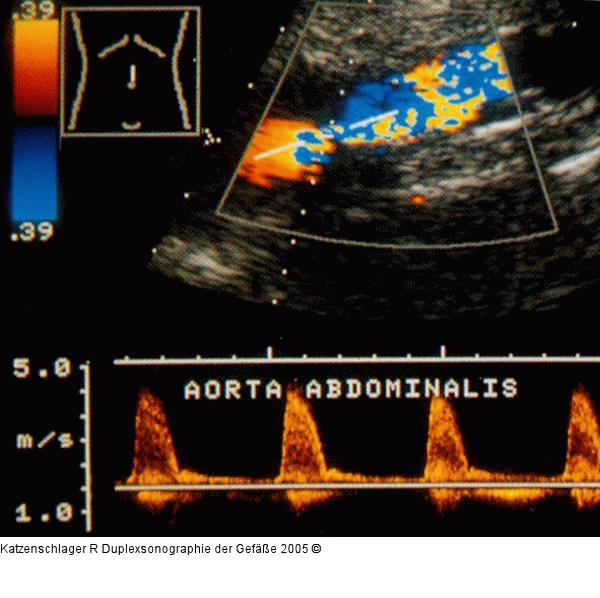

Abbildung 9: Duplexsonographie - A. abdominalis - Stenose Stenose der Aorta abdominalis (Vmax > 4 m/sec) |

Abbildung 9: Duplexsonographie - A. abdominalis - Stenose

Stenose der Aorta abdominalis (Vmax > 4 m/sec) |